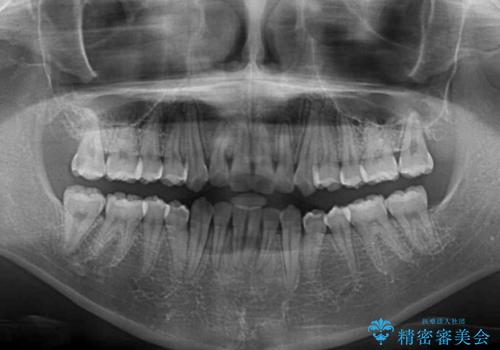

- 前歯のクロスバイトを気にして来院された患者様です。

前歯の叢生を解消するスペースを獲得するために上顎左右の親知らずを抜歯し、メタルブラケットにて矯正治療を行うこととしました。

当初は1年半程度の治療期間を想定していましたが、上下の正中を合わせていく過程で奥歯の咬みにくさが続いてしまい、2年以上の治療期間を要することとなりました。